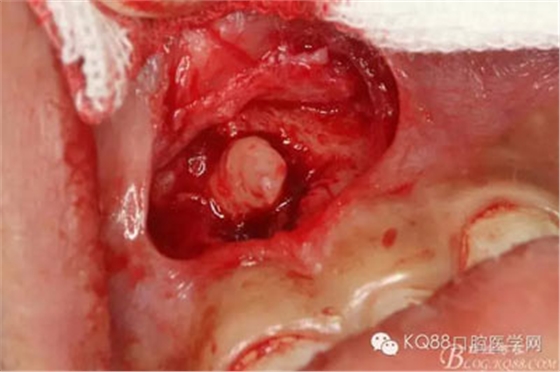

圖9.通過(guò)CBCT精準(zhǔn)的精準(zhǔn)定位,找到了倒置多生牙的牙根

圖10.微創(chuàng)牙挺在牙根四周增間隙,逐漸抬起多生牙的牙根

圖11.倒置多生牙冠部膨大,考慮接近鼻腔,不在翻大瓣、去大量骨,而是通過(guò)增間隙擴(kuò)大牙冠脫位的路徑

圖12.經(jīng)過(guò)反復(fù)增間隙,牙冠即將呼之欲出

圖13.持針器夾持多生牙牙根,牽引拔除